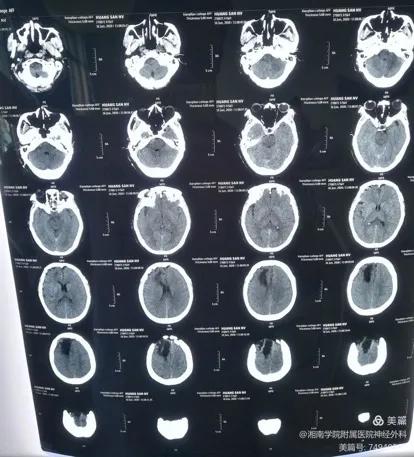

入院后,经查体发现右侧面容改变,伴口角向右偏斜,右眼裂变窄,可见频发不自主抽动。术前MR面神经血管成像显示右侧面神经有被压迫的现象。

术前

术后